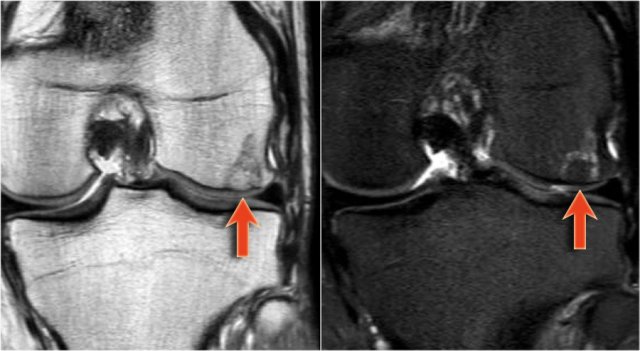

Use MRI with water-sensitive sequence (T2 FS) to determine cartilage cap thickness.

Consider progression of osteohondroma to chondrosarcoma when cartilage cap measures > 10 mm.

Growth of osteochondromas at adult ages, which is characterized by a thick cartilaginous cap (high SI on T2WI) should raise the suspicion of progression to a peripheral chondrosarcoma.

This part corresponds to a zone of high SI on T2-WI with FS on the right.

This represents a thick cartilage cap.

This is an example of progression of an osteochondroma to a peripheral chondrosarcoma.